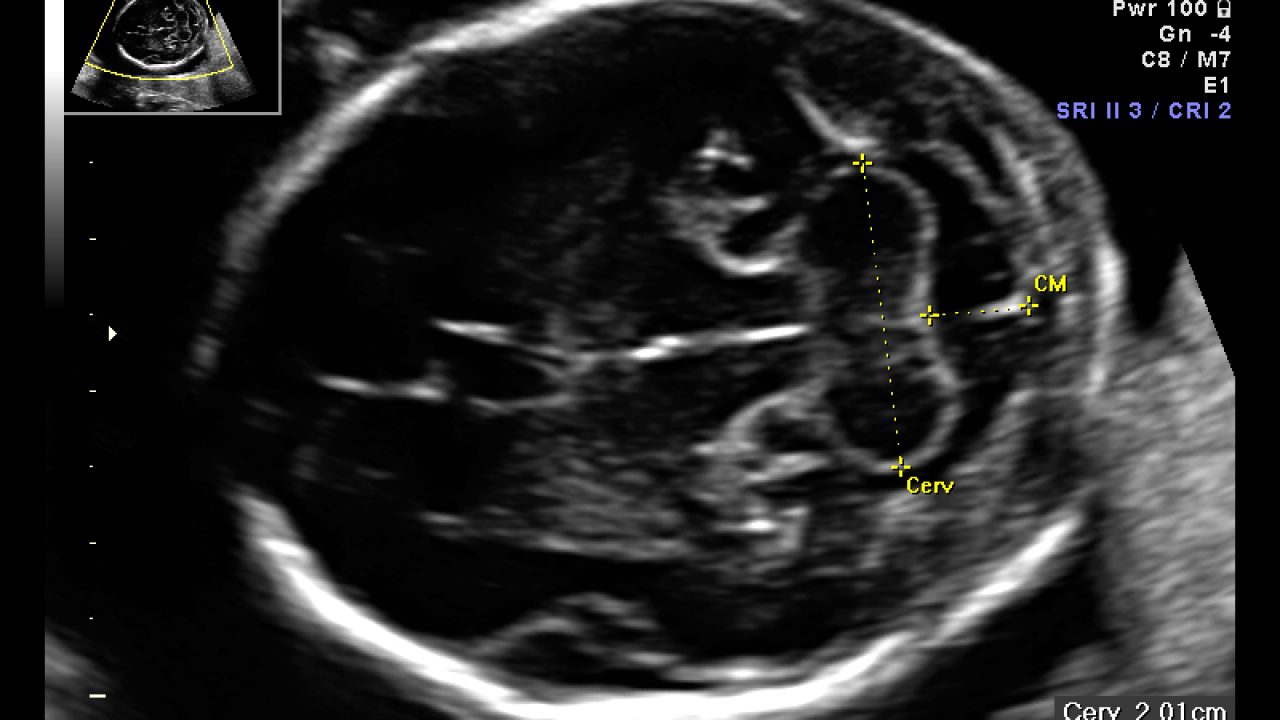

Ecografia Morfológica com Doppler minha esposa marco ultrassom morfologica so que quando chegar a data do ultrassom ela vai estar com 14 semanas e 5 dias sera q tem algum problema a moça da clinica no dia de marcar nao perguntou nd Responder Visitante Andreia 0617. Ecografia morfologica e malformazioni Con l’ecografia morfologica di secondo livello, che deve essere eseguita da operatori esperti, è possibile identificare la maggior parte delle malformazioni maggiori Non possono essere individuati invece difetti di piccola dimensione come quelli relativi al setto interventricolare o interatriale del. En el ultimo tiempo a la ecografia de las 2224 semanas "morfologica" clasica que va por el abdomen se le ha agregado una parte transvaginal para medir la longitud de tu cuello uterino Se hace como screening de parto prematuro (si esta corto, hay mas riesgo).

L’ecografia morfologica prevede la valutazione delle dimensioni del feto (biometria fetale), dell’impianto e della struttura della placenta, della quantità di liquido amniotico, del collo dell’utero, ma fornisce soprattutto uno studio analitico di tutti i distretti anatomici esplorabili nel feto. Ecografia delle 1922 settimane la morfologica L’approccio all’ecografia morfologica è sistematico, cioè si guardano gli organi in una sequenza ben definita Si parte solitamente dall’alto, descrivendo testa, torace, addome, colonna, arti. En el ultimo tiempo a la ecografia de las 2224 semanas "morfologica" clasica que va por el abdomen se le ha agregado una parte transvaginal para medir la longitud de tu cuello uterino Se hace como screening de parto prematuro (si esta corto, hay mas riesgo).